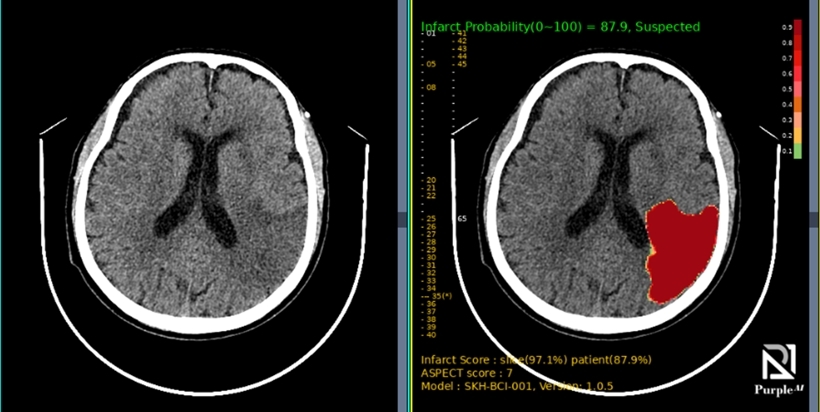

Medical Insight+ BRAIN INFARCT

Precise AI Detection

Automatically highlights suspicious regions, assigns probability scores for the likelihood of infarction, and alerts clinicians in real time.

Detects and localizes suspected infarct regions using deep learning. Marks suspected areas and provides a probability scoring directly on CT image